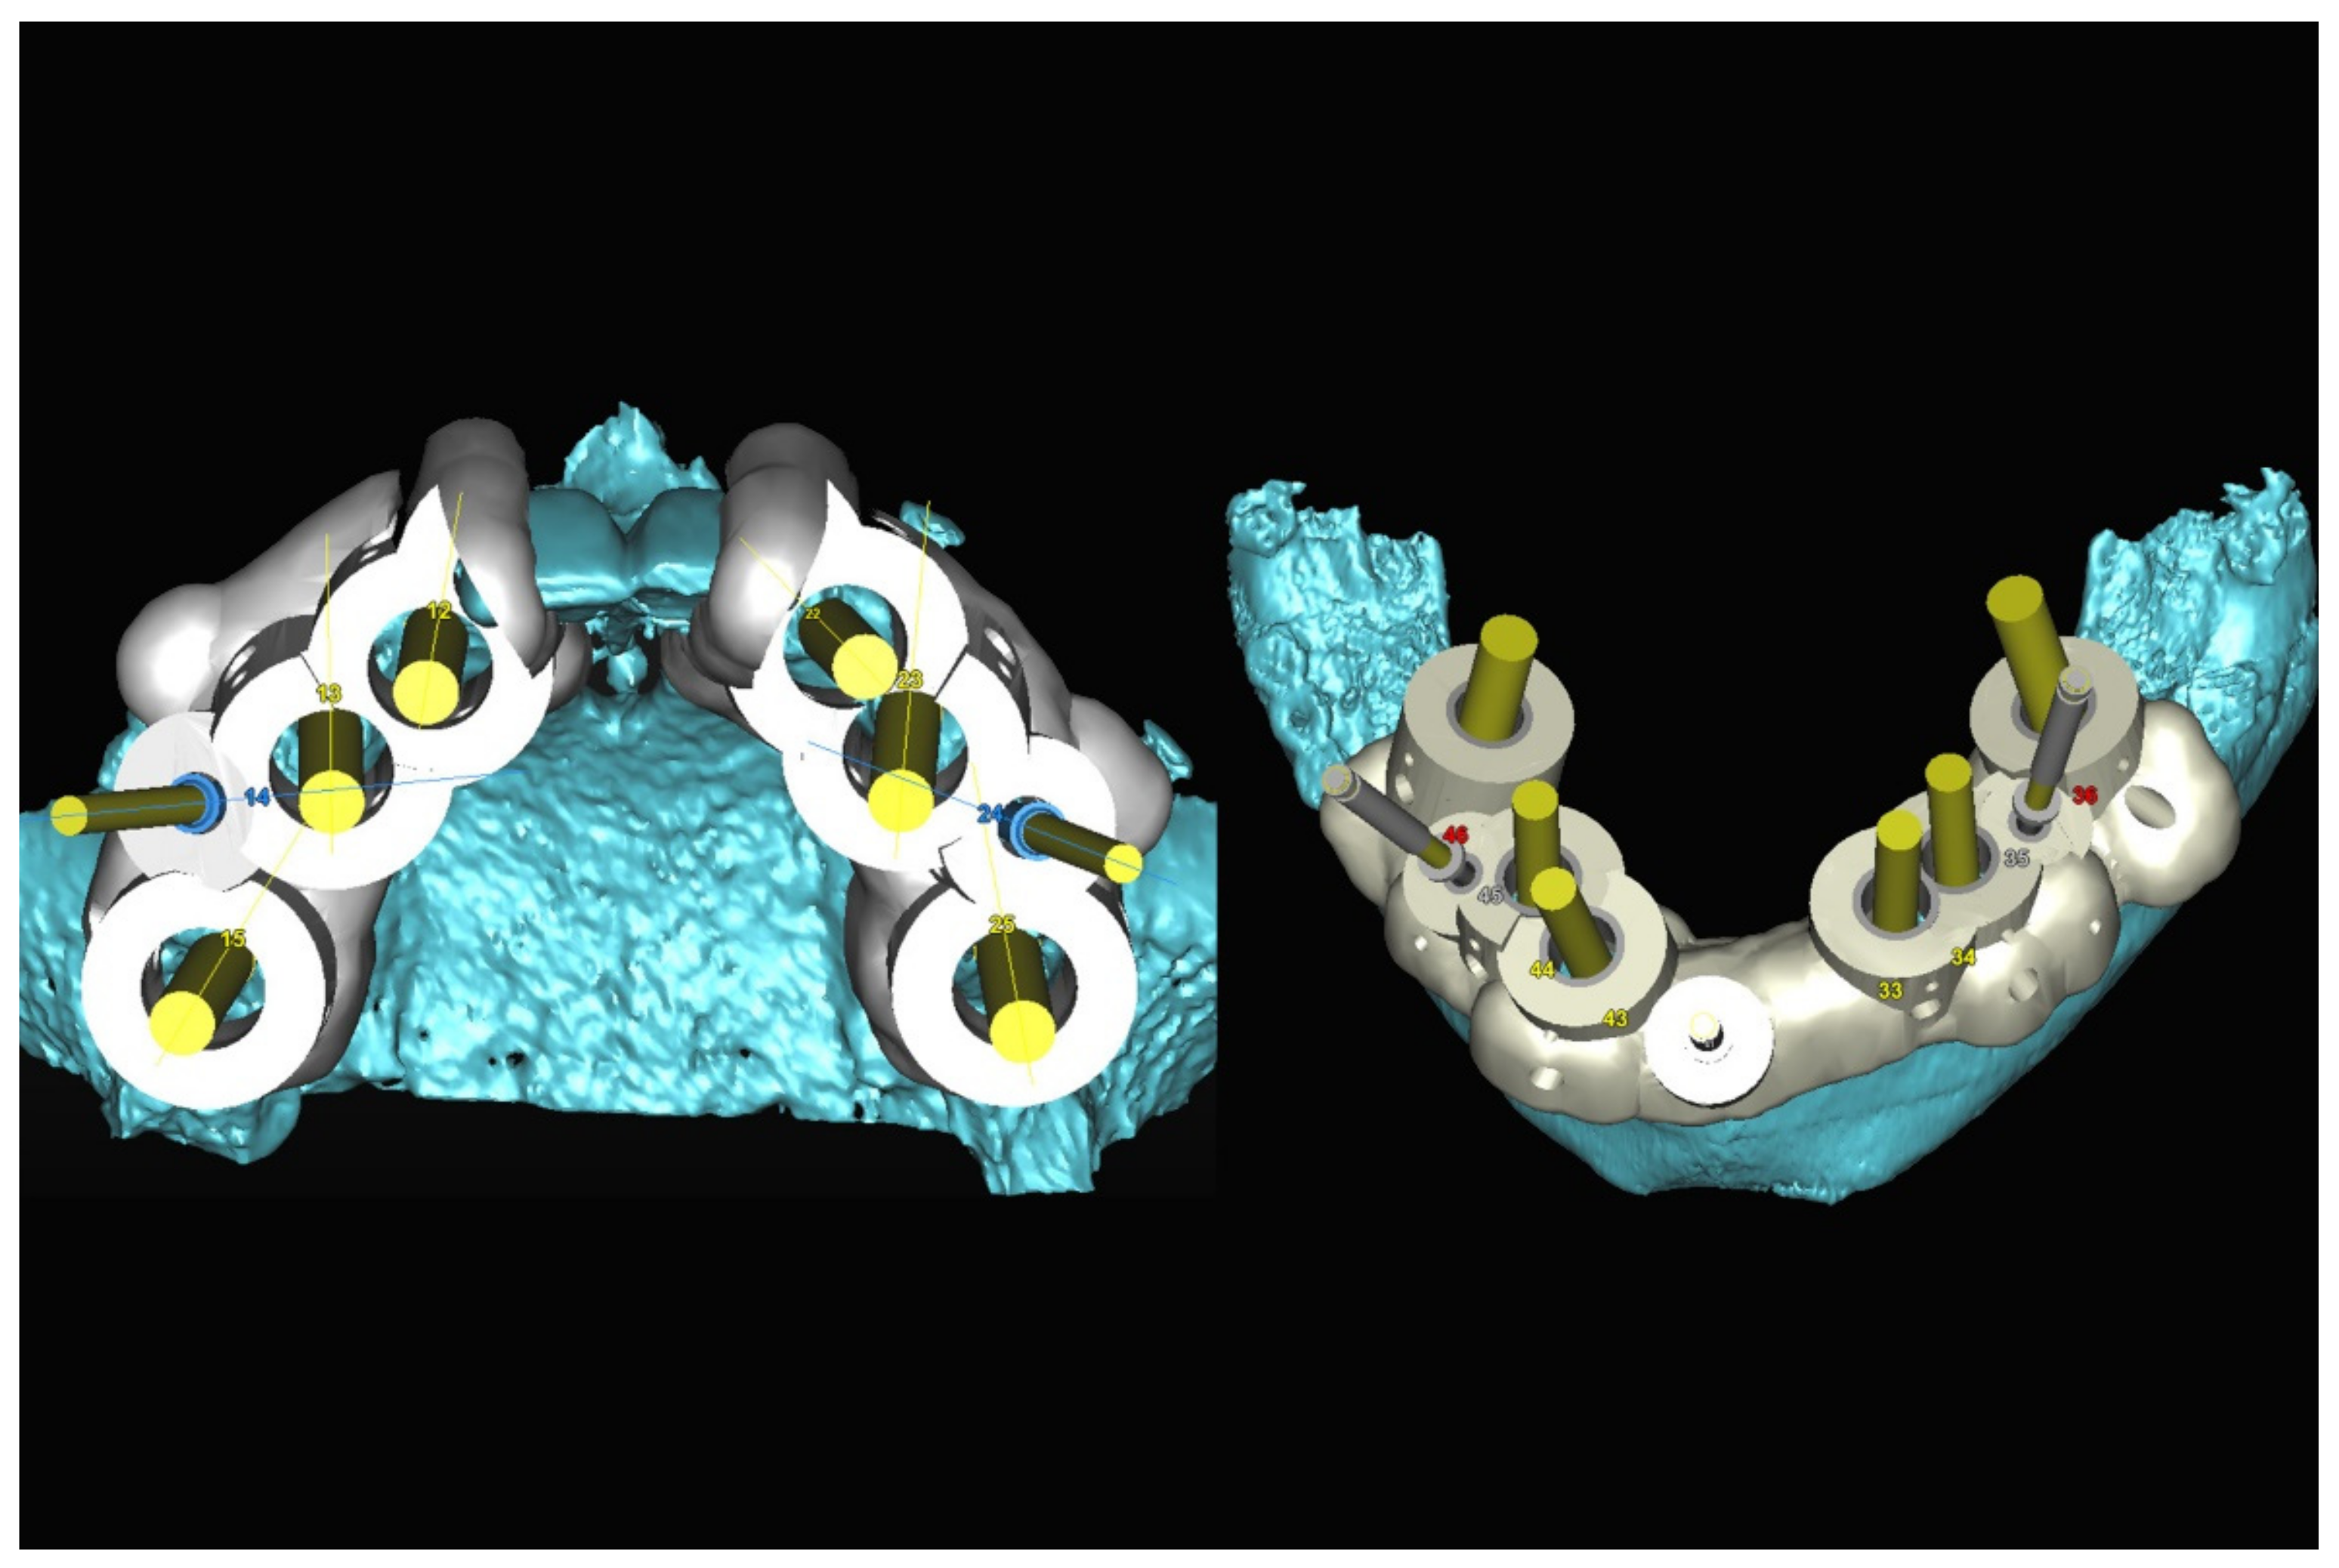

The number, the length, the diameter and the placement of computational virtual implants were determined with respect to the design of the final prosthesis the available residual bone volume and the anatomical limitations according to the previously described technical procedure (Figure 16, Figure 17, Figure 18, Figure 19, Figure 20 and Figure 21).

Figure 20.

Maxillary and mandibular virtual surgical drilling guides designed according to the implant position.

Figure 21.

Final maxillary and mandibular stereolithographic surgical drilling guides.

In March 2013, twelve guided dental implants were placed at sites # 12, # 13, # 15, # 22, # 23, # 25, # 33, # 34, # 36, # 43, # 44, and # 46 (Figure 22, Figure 23, Figure 24, Figure 25 and Figure 26)